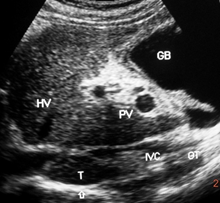

Hepatic vena cava syndrome (HVCS) a bacterial infection-induced disease of the hepatic portion of inferior vena cava that results in hepatic venous outflow obstruction (HVOO) is endemic in the country.26 The disease is seen predominantly among people of poor socio-economic background. .HVCS is a chronic disease with a long asymptomatic course. The initial lesion in the disease in inferior vena cava is a localized thrombophlebitis or endophlebitis at the site of hepatic vein openings which on resolution converts it to stenosis with development of cava-caval collaterals.27,28 The disease is diagnosed by ultrasonography and color Doppler (US/CD) examination of inferior vena cava and liver (Figure 1a&1b).29 An important clinical feature of the disease is the occurrence of recurrent acute exacerbations precipitated by bacterial infection. Acute exacerbation is marked by neutrophil leukocytosis, elevated level of C-reactive protein and ESR with mild elevation of transaminases and/or bilirubin. Severe acute exacerbation occasionally occurs with sudden development of ascites with or without pleural effusion associated with simultaneous development of bacterial peritonitis.30 Patients with recurrent acute exacerbations develop mild splenomegaly with hematological features of hypersplenism commonly neutropenia and/or thrombocytopenia.31 Acute exacerbation results in further deposition of thrombophlebitis at the site of the lesion that extends along its posterior wall and into intra-hepatic veins. Past episodes of acute exacerbations are indicated by presence in inferior vena cava of thrombophlebitis of different ages (Figure 2a–2d). Subsequent organization of the thrombophlebitis leads to development of a membrane in inferior vena cava in a few patients (Figure 2e). Recurrent acute exacerbations result in the development of thrombophlebitis, intimal thickening and stenosis of intra-hepatic veins and increase in echo-texture of the liver parenchyma that progress to cirrhosis (Figure 2e–3b). Medical management of the disease has been described.32

Figure 1a Hepatic vena cava syndrome is diagnose by ultrasonography and color Doppler (US/CD) examination of inferior vena cava and liver. This is a US/CD of young boy with CHB in replicative phase. It shows stenosis of the inferior vena cava at the site of hepatic vein opening with thick posterior wall and organized thrombophlebitis on it, the distal segment is dilated. Hepatic veins are prominent and show obstruction to blood flow at their outlets. The blood flow pattern in inferior vena cava and hepatic veins are abnormal.

Figure 1b Ultrasonography & Color Doppler of inferior vena cava and liver showing stenosis of the vein at the site of hepatic vein opening with obstruction to blood flow, distal segment dilated with presence of old organized thrombus along posterior wall. of hepatic portion. Hepatic veins prominent with obstruction to blood flow at the outlets.

Figure 1 Diagnosis of Hepatic Vena Cava Syndrome.